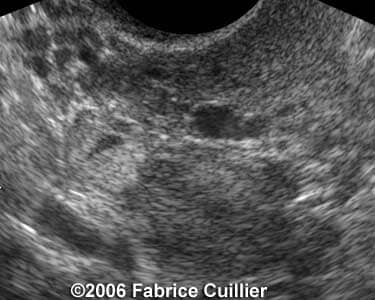

Case 3

case3a

case3b